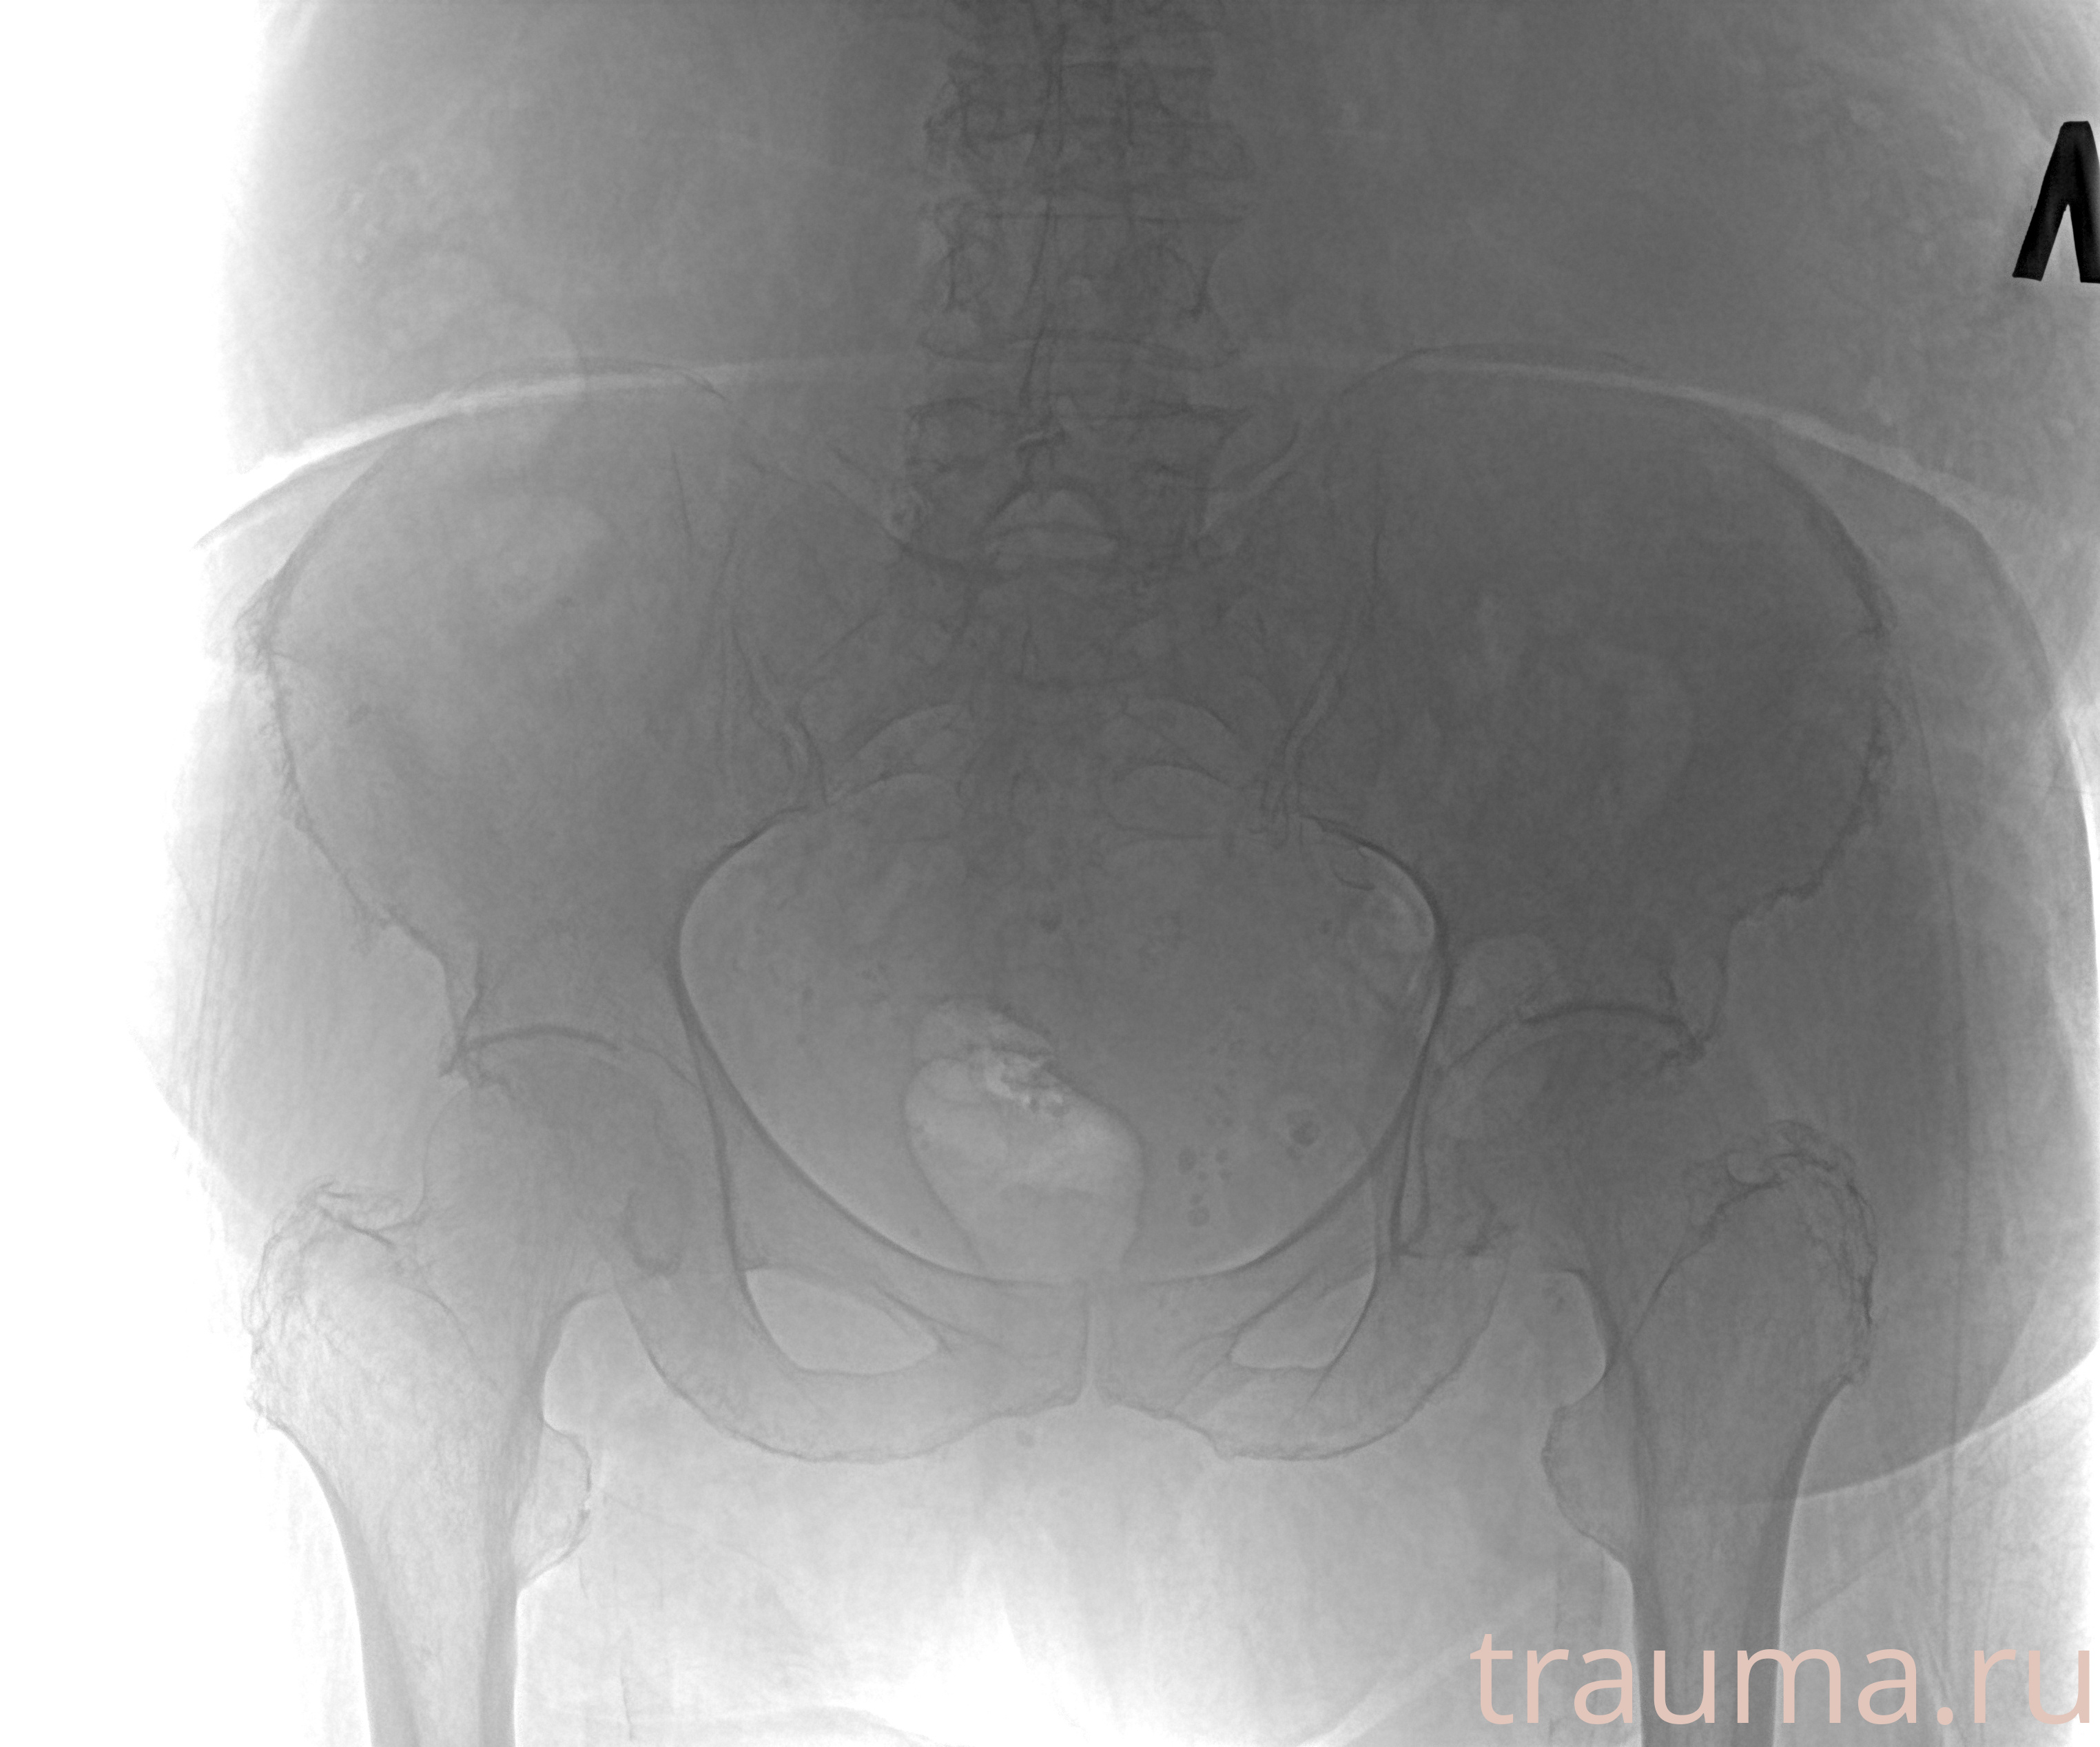

Рентгенограммы

Рентген на дому: по вашему адресу приезжает врач-рентгенолог, травматолог-ортопед с мобильным рентгеновским аппаратом, проводит диагностику травмы или заболевания, делает необходимые рентгенограммы, дает рекомендации по дальнейшему лечению. Получить качественные снимки в домашних условиях возможно благодаря уникальной методике, разработанной МосРентген Центром для института  Склифосовского

Яркость: 1   Контраст: 1   Инвертировать: 0 Увеличение: 1

Перетаскивайте мышь вверх/вниз для контраста, влево/право для яркости. Прокрутка колесом изменяет масштаб. Нажмите Сбросить для возврата к исходному изображению. При увеличении держите мышь в той области, которую хотите рассмотреть.